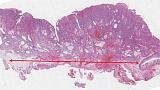

Иллюстрация №10: Рис. 10. Аденокарцинома пищеводно-желудочного перехода. Окраска Гематоксилин-Эозином, увеличение х 100. Инвазивные криброзные очаги аденокарциномы.

Иллюстрация №11: Рис. 11. Иммуногистохимическое исследование. А. Окраска мышечной пластинки слизистой оболочки маркером Десмин, увеличение х 200. Опухолевые комплексы расположены ниже окрашенной мышечной пластинки - инвазия в подслизистый слой. B. Окраска эндотелия сосу

Морфологическое и иммуногистохимическое заключение: умеренно дифференцированная аденокарцинома пищеводно-желудочного перехода, grade II (рис. 10). Опухоль прорастает в подслизистый слой (sm3), в просветах сосудов определяются очаги опухоли (Ly «+», V «+»), в краях препарата признаков опухолевого роста не выявлено, (LM «-», VM «-»), рис. 11.